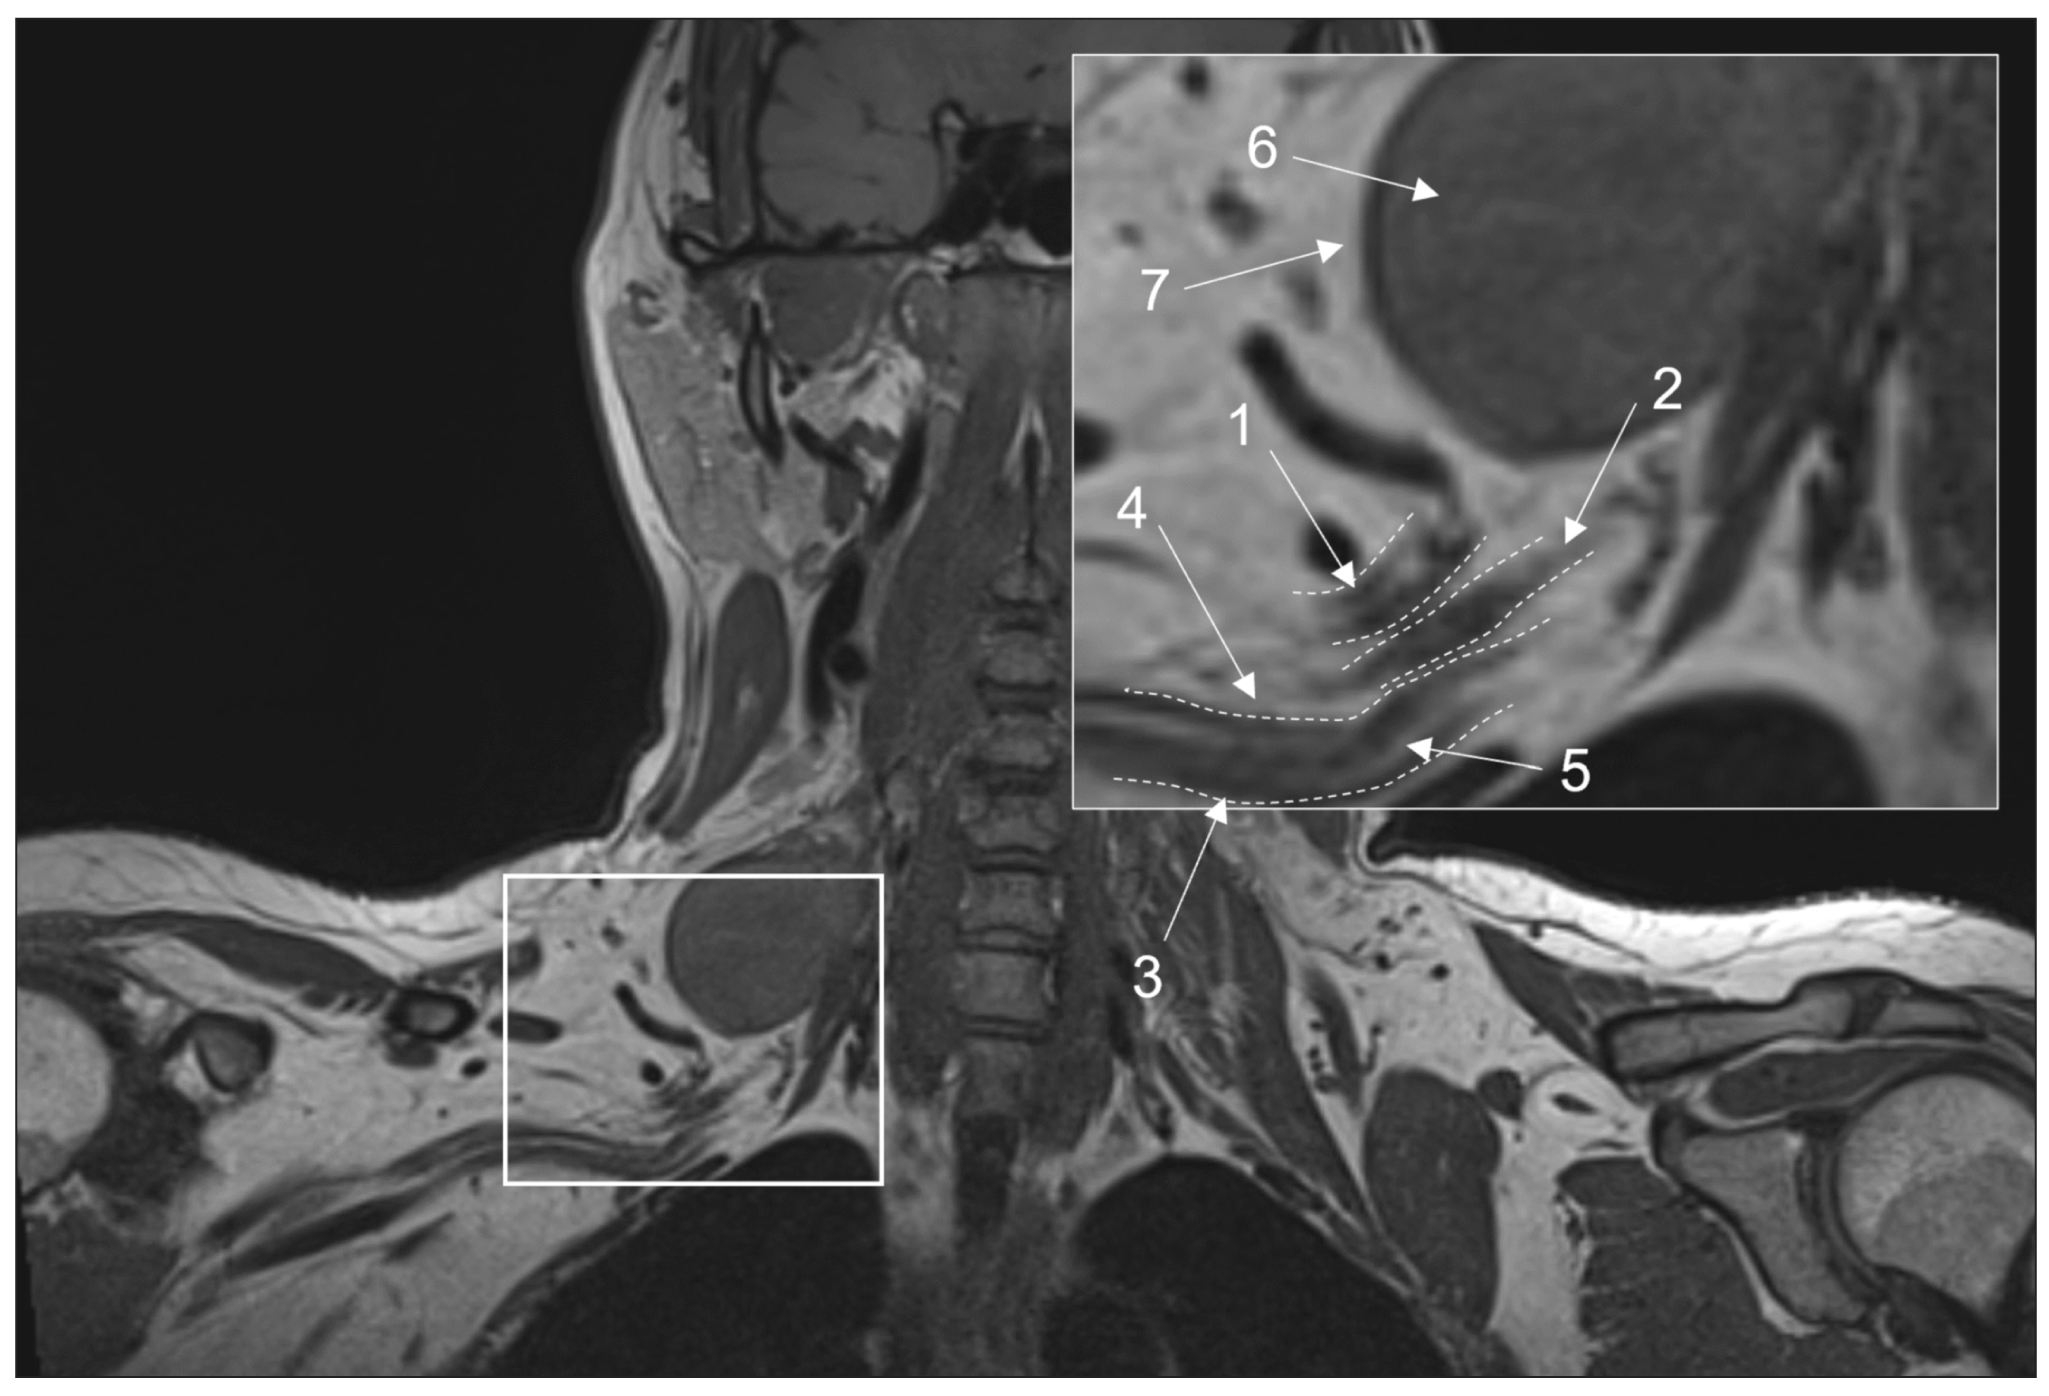

Chronic esophageal fistula as a rare cause of secondary osteomyelitis of the thoracic spine

Resumo

Infectious diseases affecting the spine are inflammatory destructive diseases that involved the organ and its structural elements as a result of infection by hematogenic, lymphogenic, or contact pathways, including may be a complication of surgical intervention. In arriving at an accurate diagnosis, it is extremely important to evaluate the anamnesis, the clinical picture, as well as the data of laboratory studies and radiation diagnostics in the aggregate.

This article presents a clinical case with the development of secondary ThVII–ThVIII vertebral spondylitis due to esophageal fistula. At the initial diagnosis, spondylitis was associated with spinal anesthesia performed six months prior to onset of the disease, as there was a fistulous defect on the skin in the lumbar region. Consequently, surgical interventions were performed three times in a surgical hospital at the place of residence. The data from the endoscopic examination, as well as the patient’s complaints regarding the relationship between meals, the appearance of pain, and the nature of the discharge from the fistula were not taken into account by doctors initially. With the help of an additional examination, including computed tomography of the esophagus with oral contrast and computed tomography fistulography, the main diagnosis was esophageal fistula. Thoracic spondylitis was only a secondary complication.

Thus, the final diagnosis of back pain and fistula in the lumbar region should be formulated after differential diagnosis with alternative diseases of the spine.